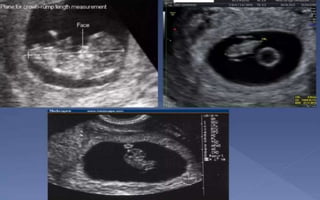

CROWN-RUMP LENGTH (CRL)

• CRL - the most accurate method to establish or confirm gestational age

(TVS - higher resolution images)

• CRL is measured in the mid-sagittal plane with the embryo or fetus in a

neutral, non-flexed position.

• Most accurate @ 7-12 weeks

• CRL EDD estimation should not be changed by subsequent scan.